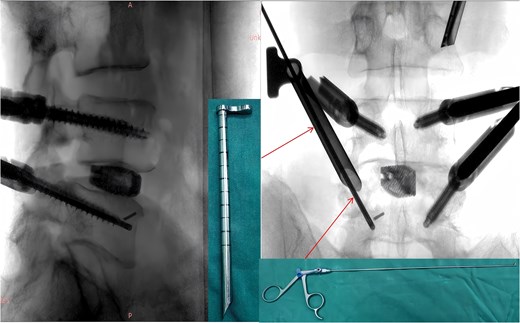

Following removal of the left L5 pedicle screw during the procedure, the smallest endoscopic sheath was inserted along with the endoscope to explore the screw trajectory. Under fluoroscopic guidance, endoscopic forcep was utilized to identify and grasp the fractured guidewire (Fig. 4). Tactile feedback of a metallic sensation confirmed precise localization. Approximately 6 mm of the fractured guidewire was successfully extracted (Fig. 5). Subsequent fluoroscopy confirmed complete removal of the broken guidewire. The left L5 pedicle screw was reinserted, and bilateral connecting rods were placed. The nuts were then securely fastened. Hemostasis was confirmed under endoscopic visualization, and the surgical incisions were closed and dressed with sterile coverings.